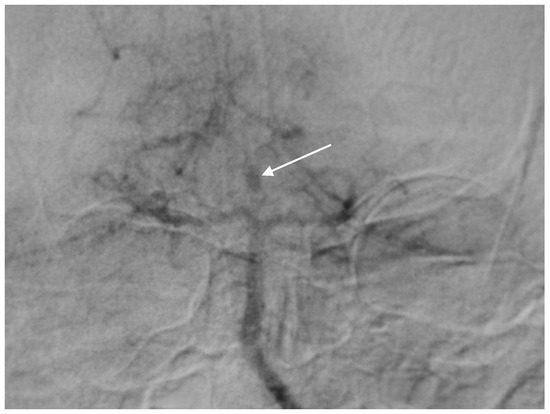

A 60-year-old woman was admitted for abrupt loss of consciousness. CT in a peripheral setting showed cerebellar hemorrhage with a pan-intraventricular hematoma in the fourth ventricle and a massive SAH in the cerebellar and spinal canal regions (Figure 4). AG revealed three aneurysms on the distal PICA (Figure 5), successfully excluded from circulation by microsurgery clipping while maintaining patency of the PICA. During the surgery, sudden intraoperative rupture occurred from the most peripheral aneurysm, located just under the arachnoid membrane on the surface of the cerebellum. After easy clipping of the neck, the feeding vessel was followed in the hematoma to its telovelotonsillar part, where another two aneurysms were visible. With the technique of temporary clipping, the optimal final position on both clips was achieved in the wide necked aneurysms. The patency was confirmed with intraoperative ultrasound. A difficult postoperative course and hydrocephalus required temporary ventricular drainage, which was converted to a ventriculo peritoneal (VP) shunt with a good long-term result.

Figure 4. Typical CT scan of subarachnoid hemorrhage (SAH) in posterior fossa with hemocephalus in the fourth ventricle.